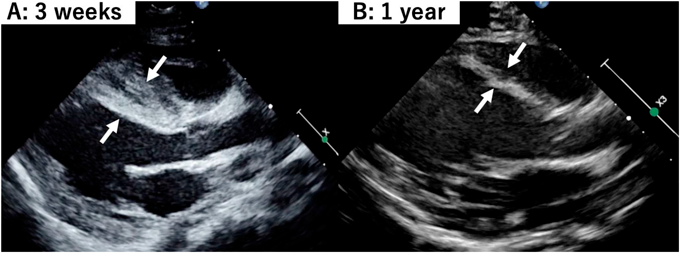

Atypical Ischemic Cardiomyopathy after Resolution of a Giant Interventricular Septal Hematoma after Repair of Ventricular Septal Defect